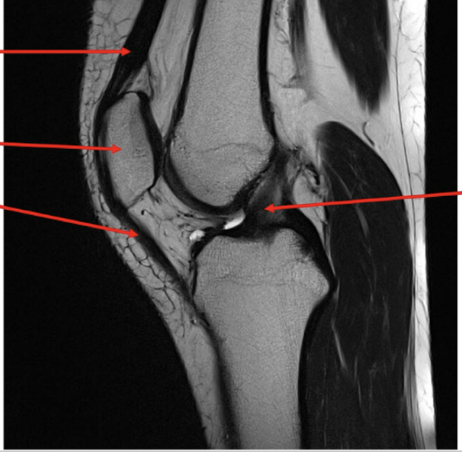

51

Pathology

• Medial collateral ligament tear

• High signal intensity within the

medial aspect of the knee indicative of fluid presence as a result of a pathological process in this case the tear.